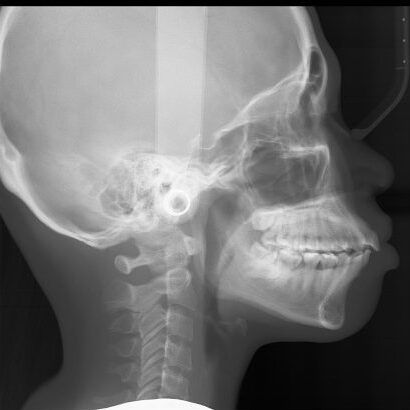

Second, it also allows the dental professional to perform frontal and lateral cephalometric exams. These exams are typically used for orthodontic care. However, they are also used for other evaluations like airway, trauma and overall facial or oral development.

Cephalometric x-ray images are most commonly needed for orthodontic treatment. However, they can also be used for TMJ assessment, sinus evaluation and trauma to the jaw or skull. A cephalometric scan captures both lateral and poster-anterior (PA) images of the entire skull, and these scans are most commonly used as part of orthodontic treatment to measure relative movement of anatomical landmarks.

A somewhat unique characteristic that many dental professionals look for in their cephalometric images is the ability to see soft tissue. Specifically, they use the image to review the relationship a patient’s jaws and teeth have to their soft tissues and the entirety of their skull.